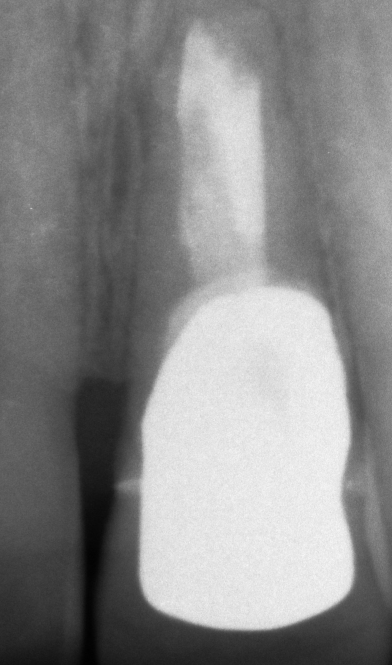

Il paziente, quando era ancora bambino, ha subito un trauma sull’incisivo centrale provocandone la necrosi e interrompendo la crescita completa della radice. Il dente è stato curato e riabilitato in modo tale da mantenerlo in arcata per più tempo possibile. A crescita completa del paziente, a causa dello stato precario dell’elemento dentario, si è proceduto con la sostituzione con un impianto osteointegrato.

PRIMA

DOPO